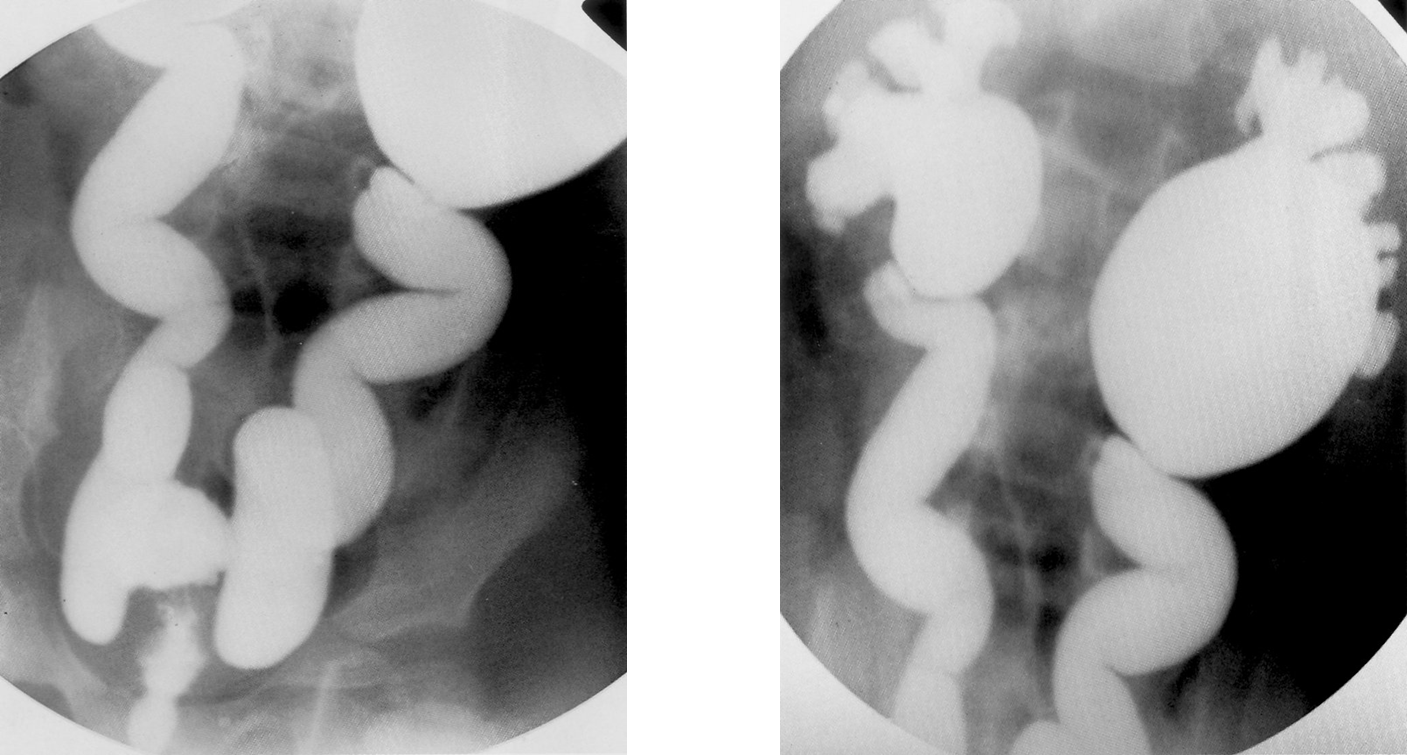

Refluxing megaureter in a voiding cystourethrogram

Contrast-filled, ballooning of the renal pelvicalyceal system (left > right)can be seen, as well as a dilated ureter with numerous kinks. This finding indicates grade V vesicoureteral reflux.